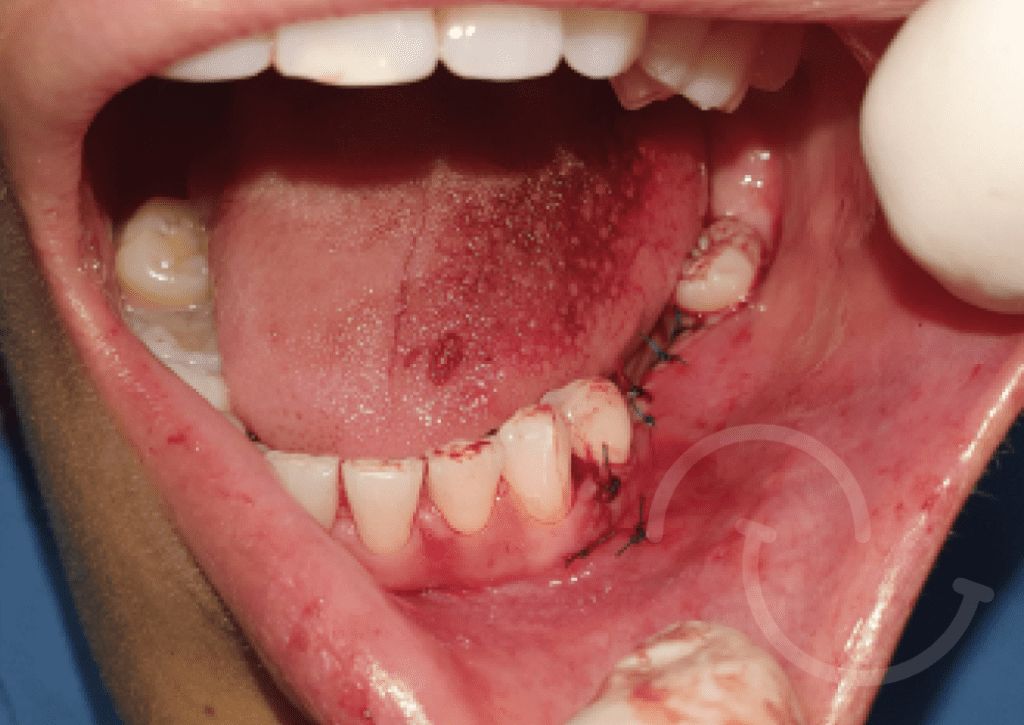

Injerto de mentón

Caso 1